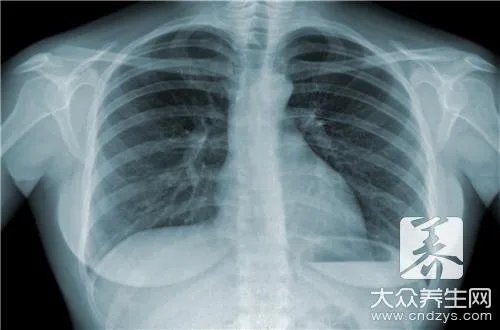

人体会出现很多种类的结核病,最为常见的就是肺结核疾病,一旦患上肺结核的话,患者最容易出现咳嗽症状,而且经常伴随着低热症状,随着病情的加重,患者的咳嗽会比较剧烈,而且会出现胸腔积液,患者的呼吸会出现明显的异常,可见结核病的巨大危害性,下面详细介绍结核病的防治知识。

结核病是由结核杆菌侵入人体后引起的一种严重危害人类健康的传染病,具有较强的传染性,故人们对结核病产生了很强的恐惧心理。随着科学技术的进展,已经研制出十数种有效的抗结核药物,只要早期发现,正规治疗,是完全可以治愈的。结核杆菌可以侵入人体任何器官,也就是说人体的各种器官都可以发生结核病,但结核杆菌主要通过人体的呼吸道进行传播,所以在人体感染结核杆菌后发生肺结核者占绝大多数。因此,“防控结核,人人有责”。